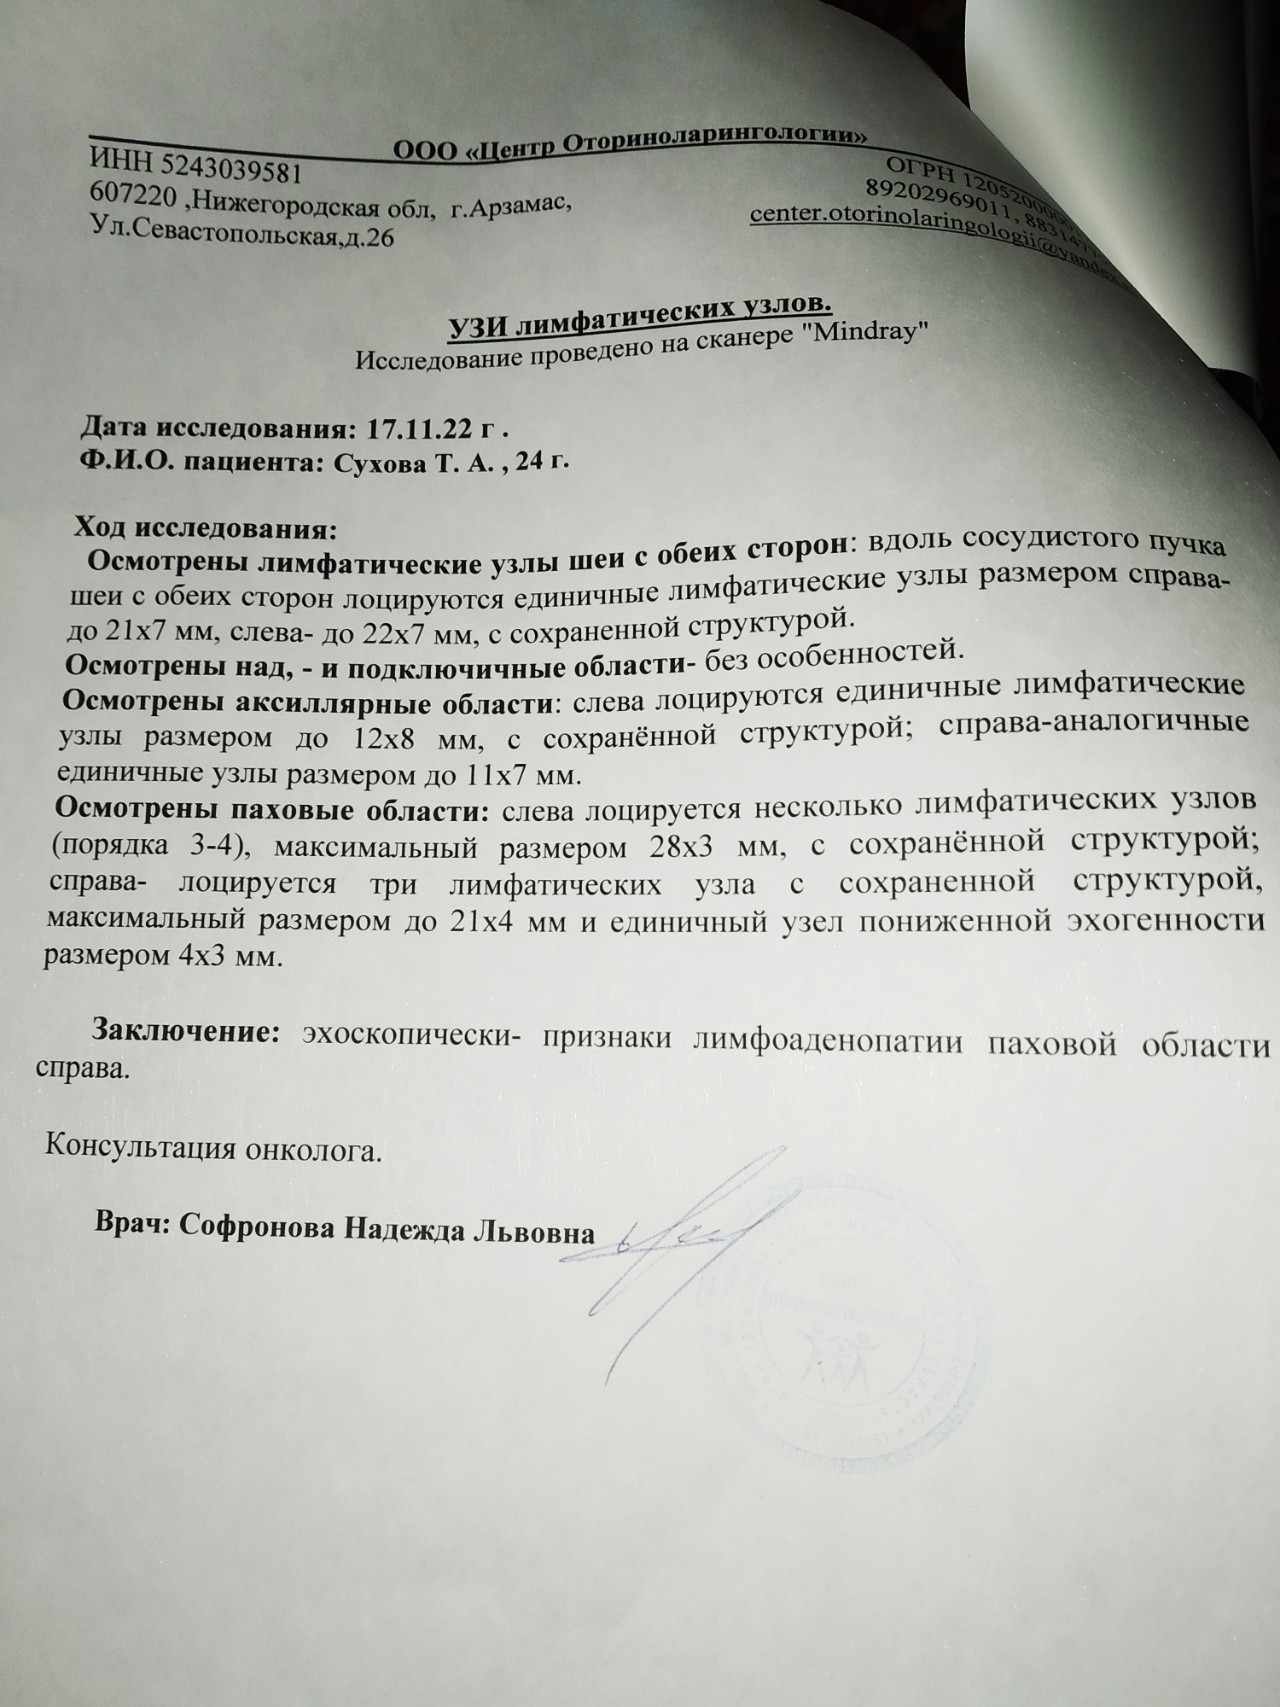

УЗИ лимфоузлов при лимфоме Ходжкина

Раздел: Образы вокруг